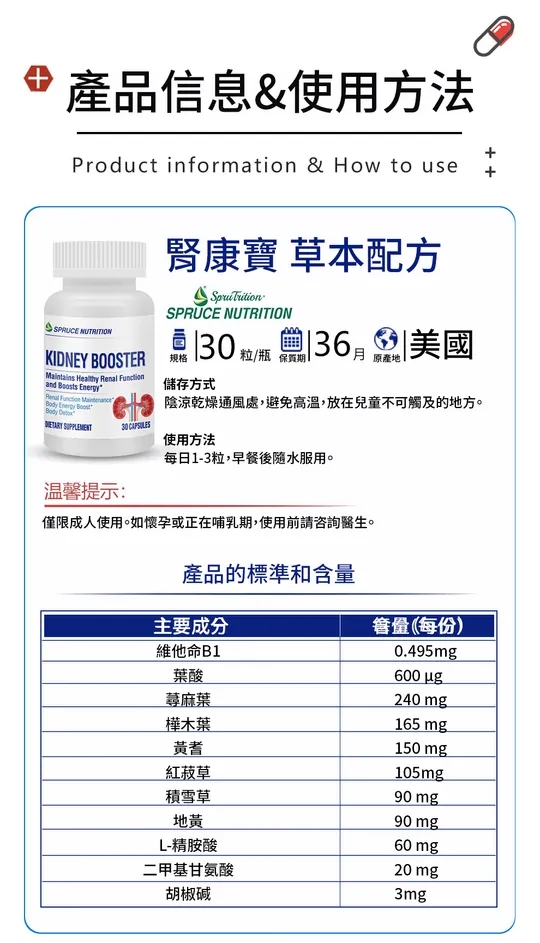

【江守山推薦】美國原廠進口雲杉腎康寶,拯救腎的新科技,有效治療糖腎、尿蛋白、尿酸、高腎、腎虛、肌酐高、腎囊腫、腎衰竭等各種腎疾病,全面改善你的腎臟功能,增強體質!告別腎病綜合徵、各類腎小球腎炎、慢性腎髒病、尿毒症等腎疾病!不透析,不洗腎,有效恢復腎功能!

讓你[安心服用]的標準!

100%安全 100%有效 100% 沒有副作用

▼GRAS 等各種權威認證,是FDA最高等級!▼

用上就見效,一瓶腎氣足,兩瓶排出體內毒素,三瓶五瓶修復鞏固腎功能

恢復腎臟功能,0激素0風險

【雲杉腎寶片】是一種新型的治療腎病新方法——0激素0風險,見效快!好的徹底!

【雲杉腎寶片】能有效的改善修復腎功能,增強體質,解決腎疾病帶來的痛苦。

【雲杉腎寶片】有效治療:糖腎、尿蛋白、尿酸、高腎、腎虛、肌酐高、腎囊腫、腎衰竭等各種腎疾病。全面改善你的腎臟功能,增強體質!

腎寶片有專業權威認證,100%安全有效,無添加防腐劑和重金屬的成分,絕對安全服用。